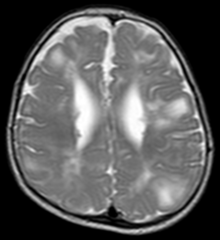

Classic intracranial manifestations of tuberous sclerosis include subependymal nodules and cortical/subcortical tubers.[5]

The tubers are typically triangular in configuration, with the apex pointed towards the ventricles, and are thought to represent foci of abnormal neuronal migration. The T2 signal abnormalities may subside in adulthood, but will still be visible on histopathological analysis. On magnetic resonance imaging, tuberous sclerosis patients can exhibit other signs consistent with abnormal neuron migration such as radial white matter tracts hyperintense on T2WI and heterotopic gray matter.

Subependymal nodules are composed of abnormal, swollen glial cells and bizarre multinucleated cells which are indeterminate for glial or neuronal origin. Interposed neural tissue is not present. These nodules have a tendency to calcify as the patient ages. A nodule that markedly enhances and enlarges over time should be considered suspicious for transformation into a subependymal giant cell astrocytoma, which typically develops in the region of the foramen of Monro, in which case it is at risk of developing an obstructive hydrocephalus.

A variable degree of ventricular enlargement is seen, either obstructive (e.g. by a subependymal nodule in the region of the foramen of Monro) or idiopathic in nature.